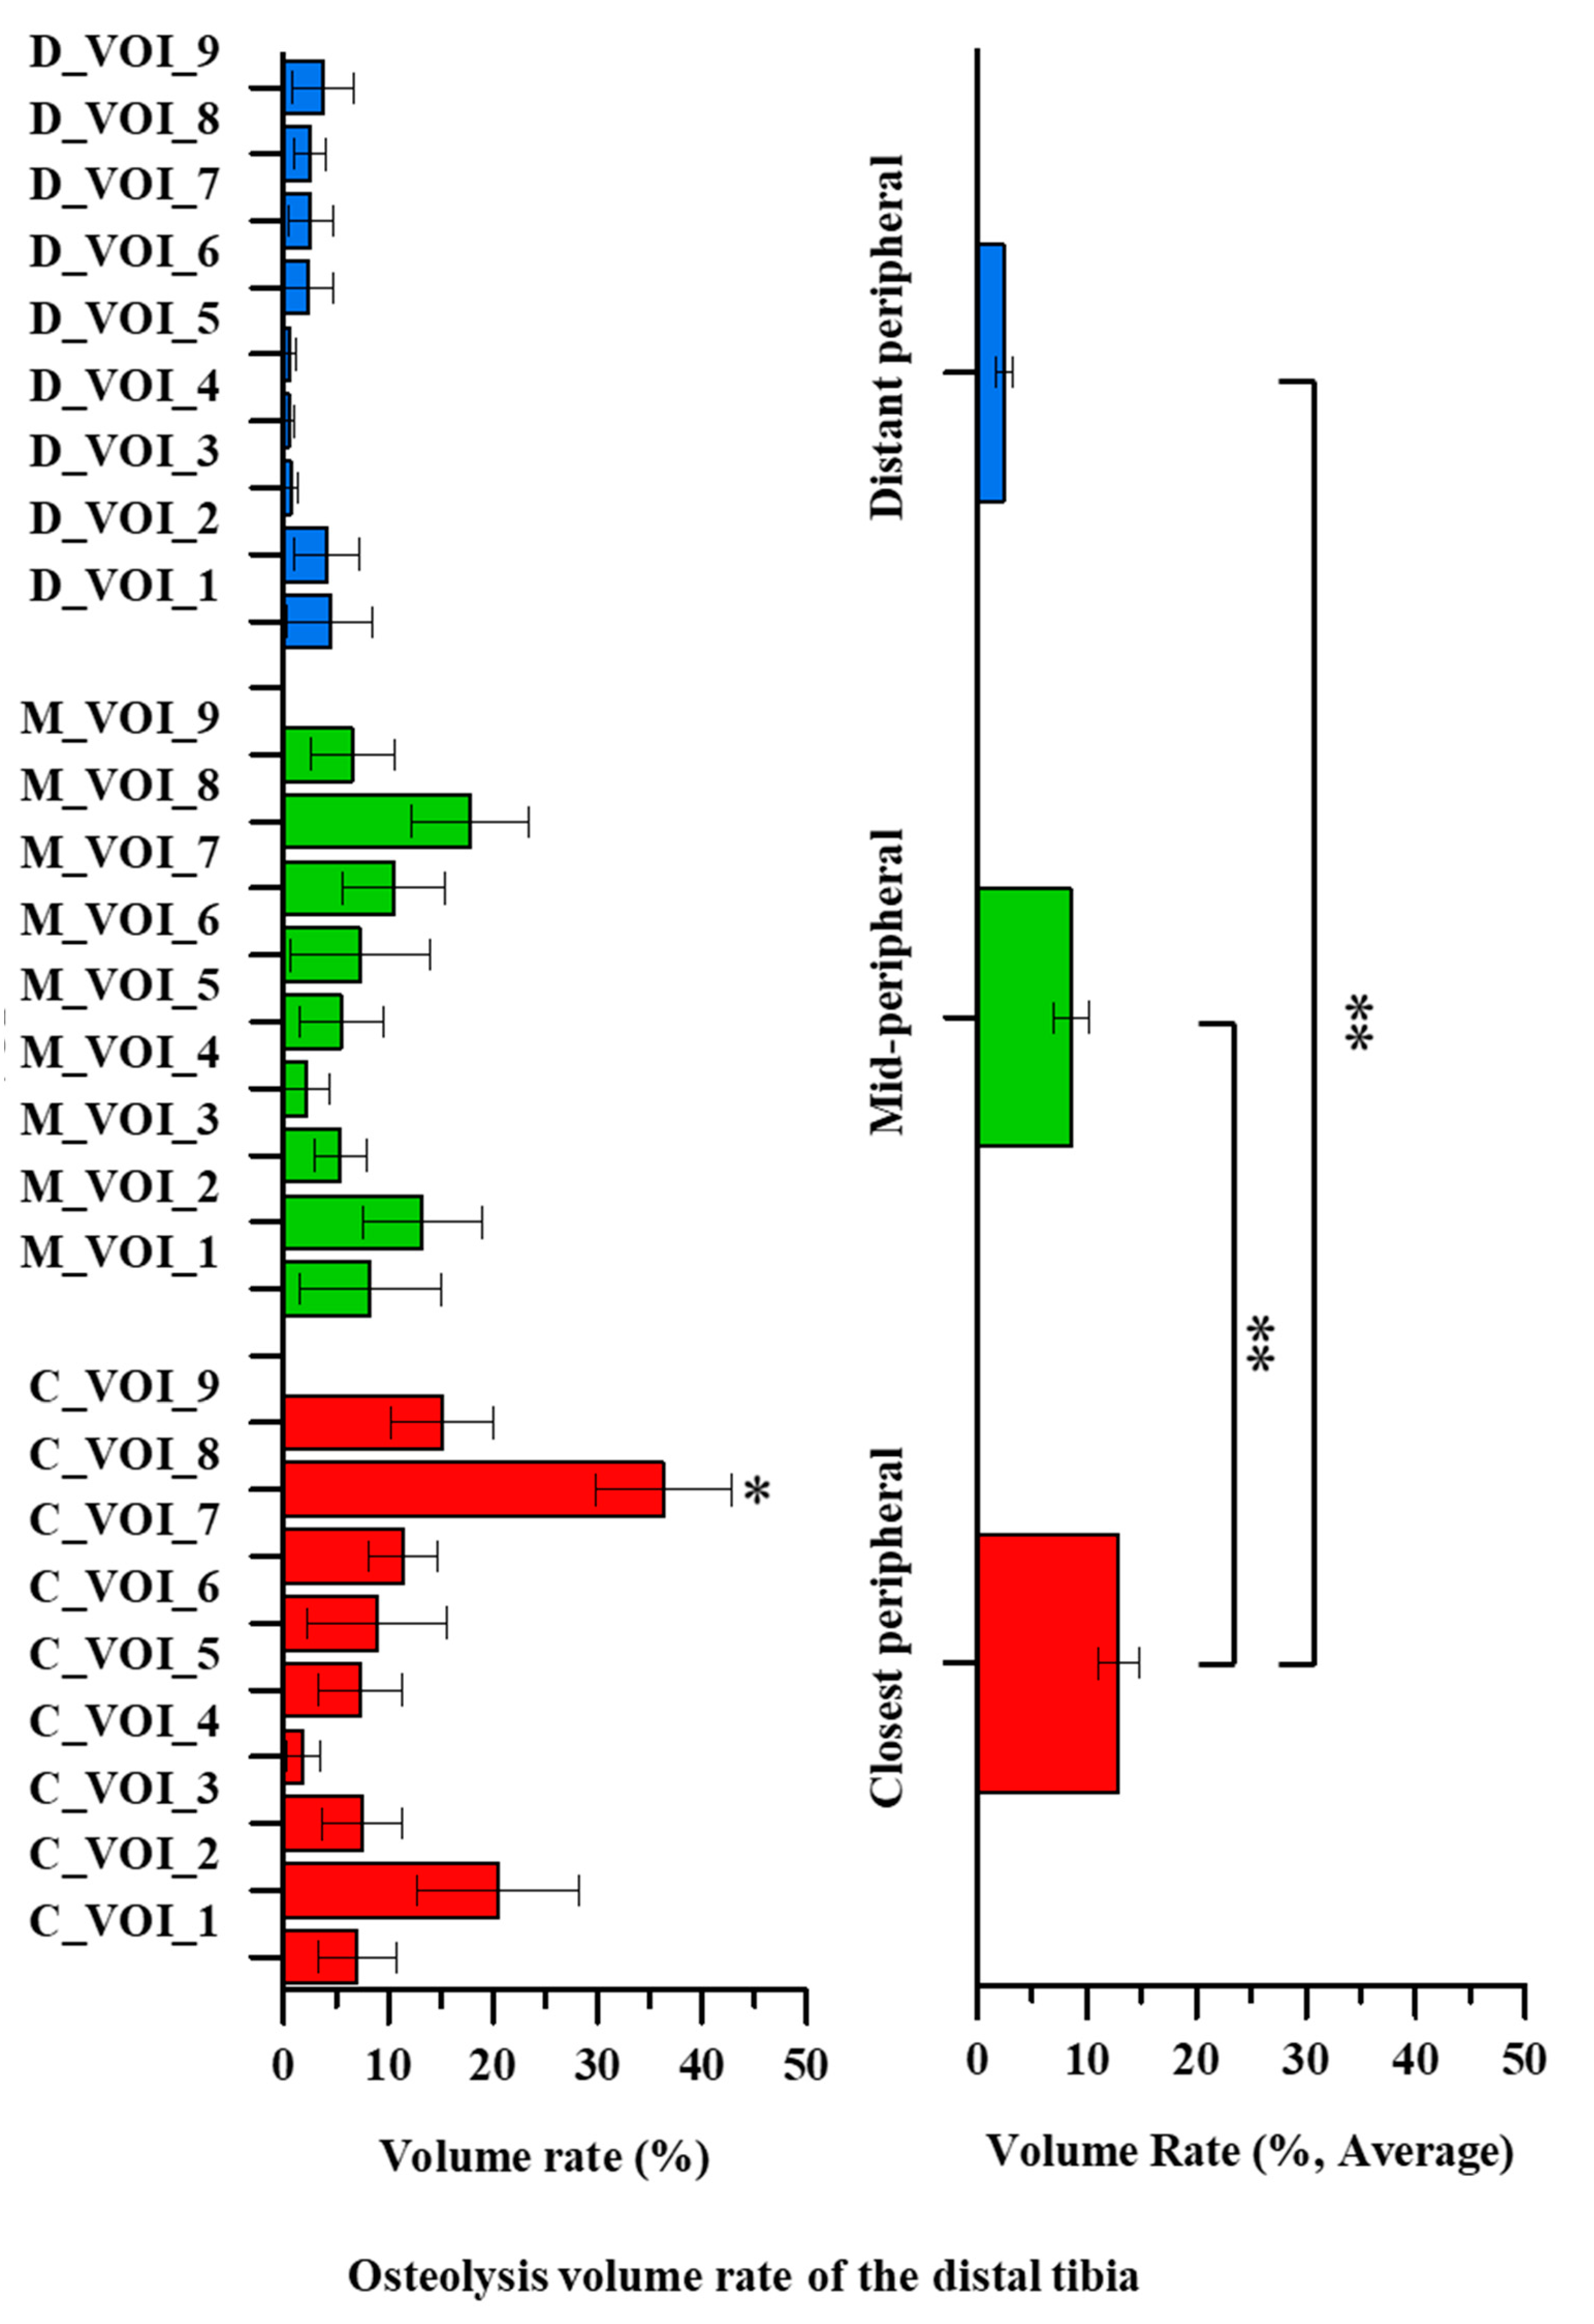

3. Results